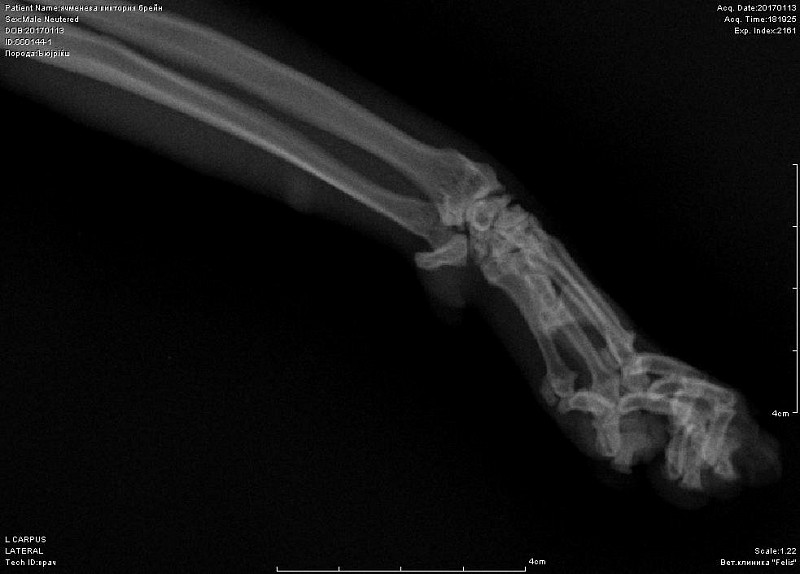

Периодически хромает после долгого лежания.Около 10 дней хромота не прошла, стал не наступать на переднюю лапу-ходит на трех. Повели в к врачу, при осмотре спокоен. Сделали снимок-врач сказал, что был когда-то компрессионный перелом лучевой кости, сказал, что кот хоить нормально больше не будет. Нужно еще мнение, посмотрите снимок, пожалуйста.

Добрый день! не вижу перелома на этом снимке. Нужна еще прямая проекция. Боль именно в запястном суставе?

К сожалению не знаем, где болит-реакции на пальпацию и энергичные движения в суставах не выявили. Именно на этом снимке врач мне указал на компрессию кости-как он сказал кость посередине должна быть квадратная, а она стала треугольной... Я сама нашла атлас посмотрела, что это нормальный вид лучевой кости.

Может быть Вы видите что-то не то на этом снимке? Может сустав? Мы были у другого врача, он снимки читать не может, сказал, что вроде не видит перелома, но точно сказать не может- предположил заболевание сустава-уколы нестероидные, кальций и пьем страйт глюкозамин с хндроитином. Второй врач зафиксировал лангеткой ногу коту. Других снимков не записали, хотя я видела в прямой проекции.

вот в запястном суставе не вижу изменений.А вот локтевом есть признаки артроза. Но все же это не прямая и даже не боковая проекция локтя.